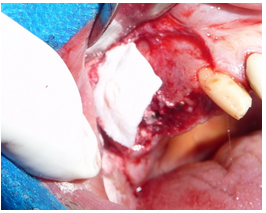

É realizado o preenchimento parcial prévio da cavidade sinusal com biomaterial. Existem vários biomateriais com resultados excelentes, consagrados na literatura. Neste caso específico foi utilizado o Osteogen® (figura 7).

No defeito ósseo na região do elemento 16, causado pela exodontia, foi utilizado biomaterial (Osteogen®) e a abertura da janela de acesso foi coberta com curativo de colágeno Collacote® (figura 9).